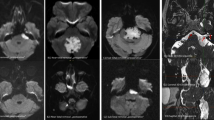

Figure 2 presents the results of the 8 meningioma patients at different time points in each category (attention, memory, and executive functions).

Plots for the 8 meningioma patients in selected subtests of the attention (left), memory (middle), and executive functions (right) categories.